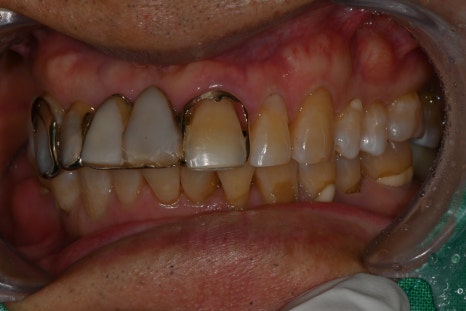

Prosthetic Treatment and the Final Steps

The final stage of implant treatment is the prosthesis.

The prosthesis is

The part that functions as the actual tooth,

and it is made to match the patient’s bite and shape.

In this case,

a custom abutment and a zirconia crown were used.

Molar implants are under strong chewing force in particular,

so bite adjustment is very important.

At the implant dental clinic, stability is ensured by checking the bite multiple times. Implant price can also vary depending on